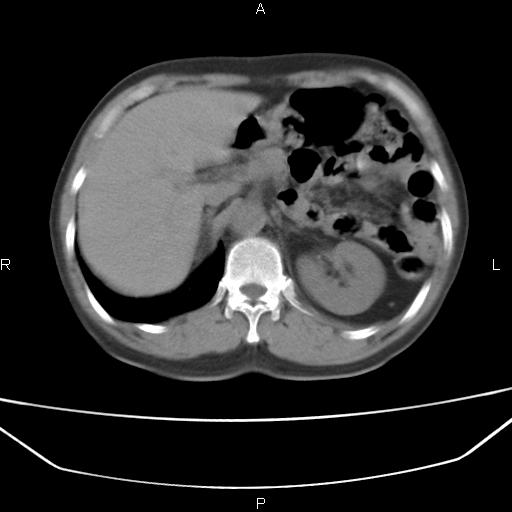

患者,男。50岁。近几日有咳嗽症状,无其他不适,既往病史无,考虑膈疝。请前辈们看看指导指导。

膈膨升,左下肺通气不良,膈肌好像还完整。

考虑左侧膈疝。

左侧膈疝。

符合隔膨升,膈肌较完整。